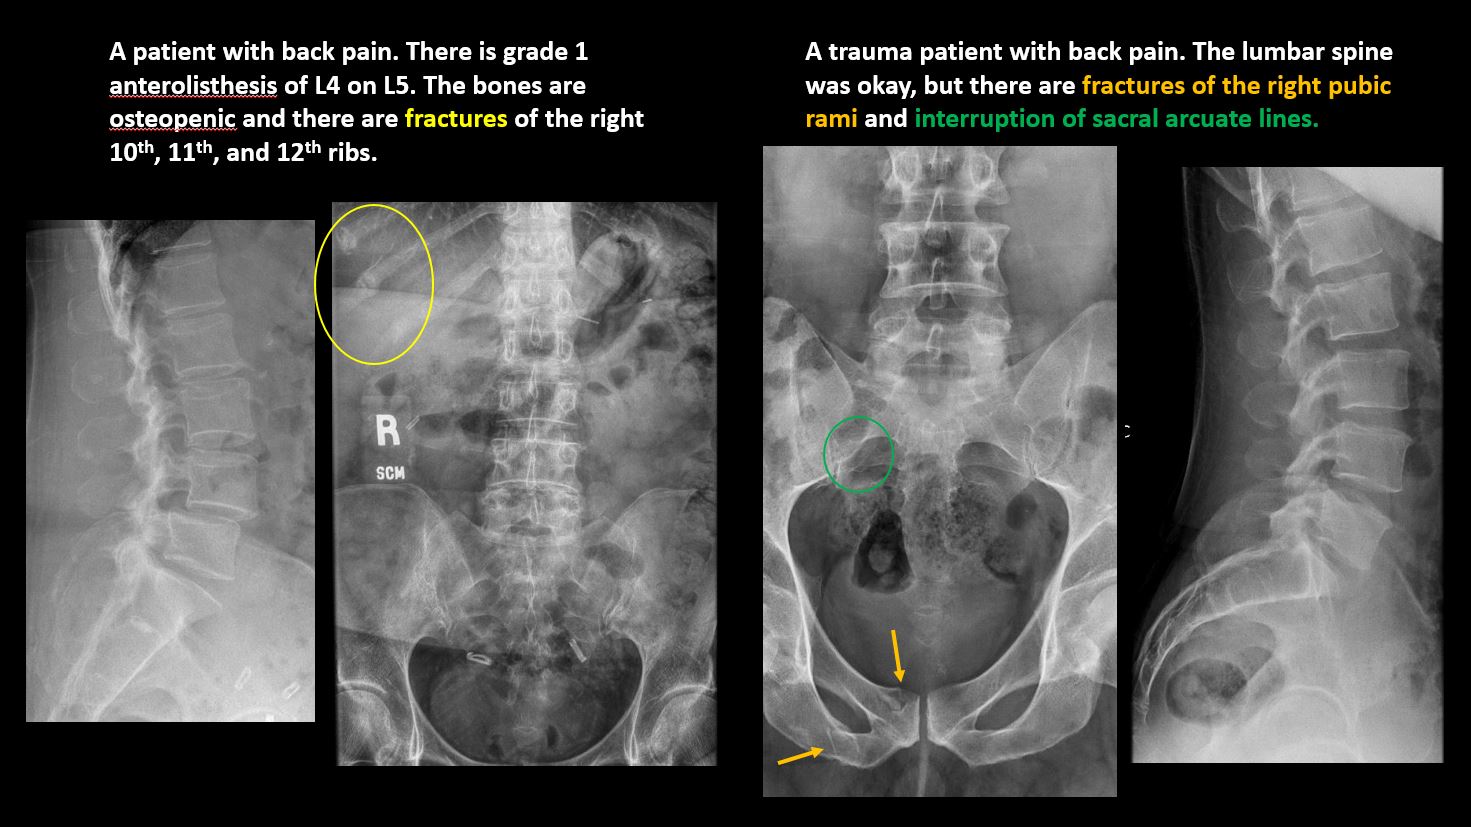

There is anterior or posterior spondylolisthesis, subluxation, or rotational abnormality at a disc space. |

No | NA |

There is a fracture or interruption of the arcuate lines of the sacrum. |

The included thoracic spine, ribs, and remainder of the bony pelvis are abnormal. |

There are gallstones, vascular, renal, pelvic, or other soft tissue calcifications present. |

Yes | NA |